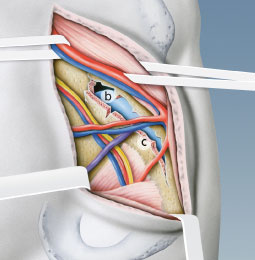

Abb. 1

Lage der verschiedenen vorderen Zugänge zur Hüftgelenkspfanne:

«Iliofemoraler» Zugang nach Smith-Petersen (schwarze Linie)

«Ilioinguinaler» Zugang nach Letournel (blaue Linie)

«Stoppa»-Zugang (violette Linie)

«Pararectus»-Zugang nach Keel (rote Linie), entlang des Musculus rectus abdominis (a)

Entwicklungsgeschichte der vorderen Zugänge

Der erste vordere Zugang zum Hüftgelenk wurde 1917 vom Norweger Marius Smith-Petersen beschrieben. Dieser sogenannte Iliofemorale Zugang führt entlang der Beckenschaufel und vorne über das Hüftgelenk (Abb. 1). Er wird heute nur noch bei Frakturen der Vorderwand der Hüftgelenkspfanne eingesetzt. Der untere Anteil des Schnittes direkt über dem Hüftgelenk entspricht zudem dem heutigen minimalinvasiven vorderen Zugang zur Implantation einer Hüfttotalprothese. In den 60er-Jahren etablierte der Franzose Emile Letournel den «ilioinguinalen» Zugang. Er verläuft entlang der Beckenschaufel und dem Leistenband und ist heute noch der Goldstandard. Beide erwähnten Zugänge erfolgen jedoch von aussen über die Beckenschaufel, und die Sicht auf den typischerweise bei alten Patienten nach innen verschobenen Pfannengrund ist nicht möglich. Deshalb führten der Finne Hirvensalo und die Amerikaner Cole und Bolhofner 1994 den «Stoppa»-Zugang ein, um eine bessere Sicht und entsprechende Repositions- und Fixationsmöglichkeiten zu haben. Dieser Zugang basiert auf der Versorgungstechnik von Leistenhernien, 1973 beschrieben vom Franzosen René Stoppa, und muss häufig mit dem Zugang an der Beckenschaufel kombiniert werden.